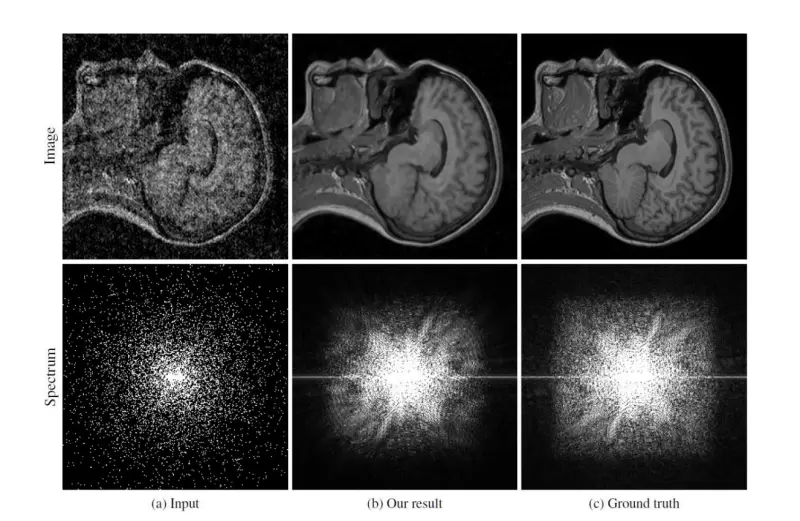

(a)人工加噪点图片(b)AI处理后(c)原图

据悉,科研人员使用了IXI数据库中的5000张、来自50个研究对象的磁共振照片来训练Noise2Noise对MRI图片的处理能力,处理过的MRI图片没有了人工噪点会看起来比原图更模糊一些,不过还是恢复了一些清晰度。